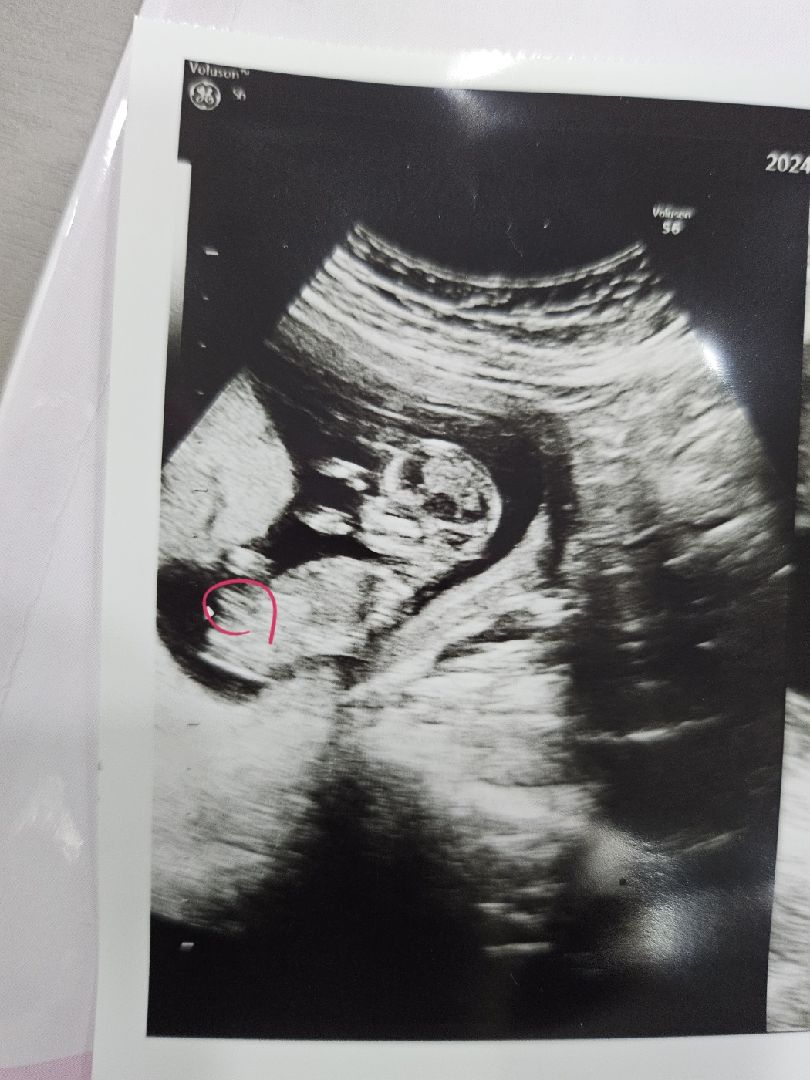

13주입니다 요게생식기인가요?

의사샘이 1도안알려줘서ㅠㅠ 저동그라미친곳이 생식기 맞을까요 아닐까요..? 생식기가 맞다면 각도법 아들인데 맞아보이나요?

각도법은 조심스레 아들에 한표욤 👼🏻♥️

아들이신것 같네요~ 축하드려요~

그렇게 보이긴 하네요 ㅎㅎ